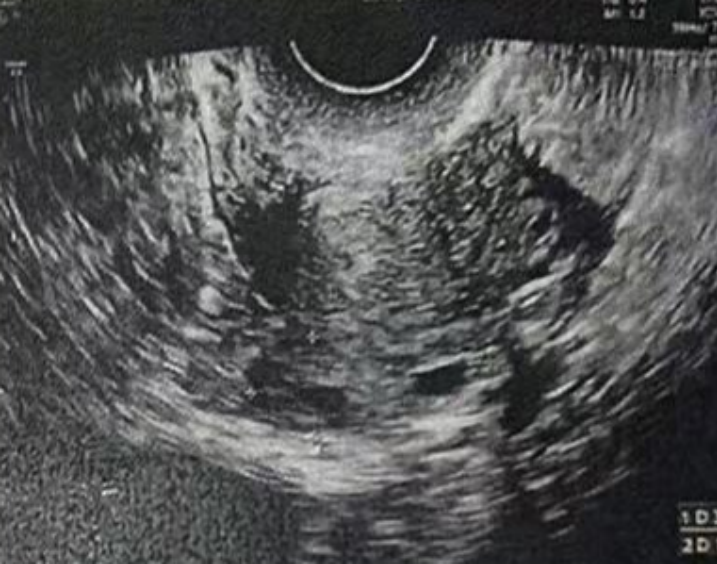

子宫内膜厚度:4.6 毫米,子宫有瘢痕大小 0.76*0.19 厘米

雌二醇:241 pg/mL

孕酮:0.13 ng/ml

子宫内膜厚度:9.3-10 毫米

- 有粘液滞留在腔内,从峡部瘢痕延伸至子宫底

- 双卵巢无囊肿

- 计划在胚胎移植前重复超声检查以冲洗峡部瘢痕

雌二醇:210.52 pg/mL

孕酮:0.3 ng/ml

子宫内膜厚度:8.9 毫米